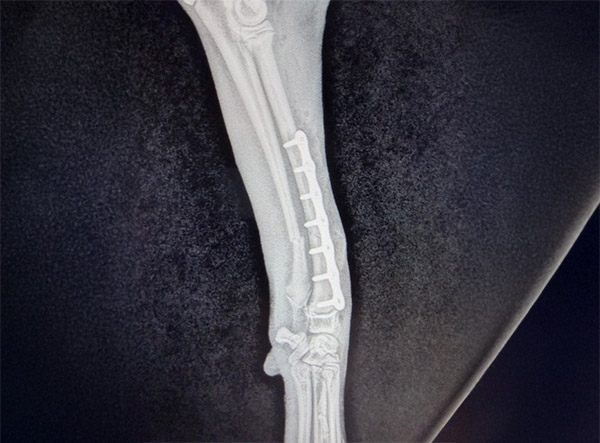

In November 2025, Skeeter, a 14-week-old Doodle puppy weighing 9.4 lbs (4.3 kg), was brought in after an accident on November 12th. He had sustained a mid-shaft fracture of both the radius and ulna in his left forelimb, an injury that can be particularly concerning in young, growing dogs.

The procedure was performed by Dr. Jeff Mayo. To restore alignment and stability, both the radius and ulna were repaired through bone plating. A 2.0 mm titanium LeiLOX locking plate system was selected to provide secure fixation appropriate for a small, developing patient. Attention was given to preserving soft tissues and maintaining proper positioning to support healthy bone healing. Following surgery, Skeeter’s limb was placed in a splint for four weeks to protect the repair and minimize stress during early recovery.